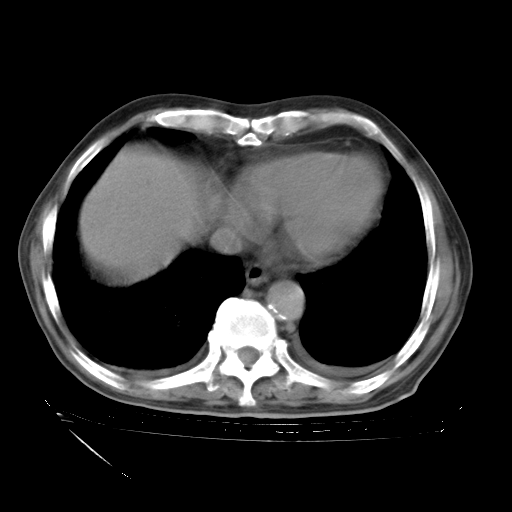

补充下:5月9日胸部CT:似乎已见双下肺胸腔积液了,鉴于目前有下肢水肿,肝功示:白蛋白低,应注意多浆膜腔积液(漏出液可能大?),需注意!

甲强龙80mg/日+抗结核治疗(异烟肼+利福霉素+乙胺丁醇)10天。复查肺部CT。

治疗10天肺部CT